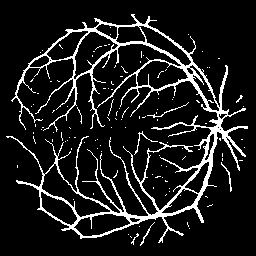

The following provides quantitative comparisons of three FCNs respectively. Example results on various image-to-image mapping tasks are shown in Figure 2.

Figure 2: Example results of three FCNs (from left to right: input, ground truth, the output of FCN-16s, U-Net and our model) on various tasks (from top to bottom: EM segmentation, vessel extraction and raindrop removal)